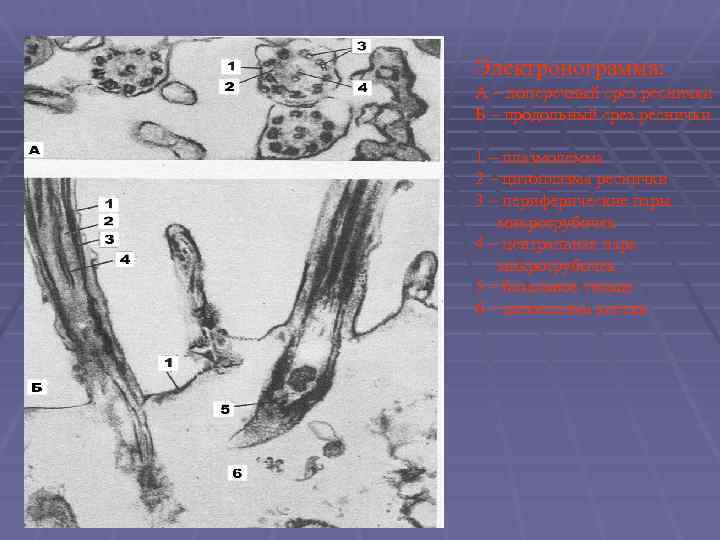

Электронограмма: А – поперечный срез реснички Б – продольный срез реснички 1 – плазмолемма 2 – цитоплазма реснички 3 – периферические пары микротрубочек 4 – центральная пара микротрубочек 5 – базальное тельце 6 – цитоплазма клетки